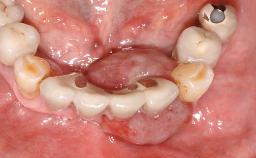

Removal of a Malpositioned Implant and Direct New Implant Placement with Simultaneous Contour Augmentation using GBR

A 35-year old female patient was referred to the Department of Oral Surgery and Stomatology at the University of Bern, Switzerland, for examination of an implant site that had exhibited clinical signs of slightly delayed wound healing. In addition, the referring clinician found no evidence for a facial bone wall when she raised a flap to gain access to the implant for abutment connection. Four months earlier, she had inserted a bone-level implant in a single-tooth gap, where the lateral incisor had been extracted due to a chronic periapical lesion on the mesial aspect of the root. Implant placement was combined with simultaneous bone augmentation using deproteinized bovine bone mineral (DBBM, Bio-Oss®; Geistlich, Wolhusen, Switzerland) and a collagen membrane (Bio- Gide®; Geistlich), followed by primary wound closure. The patient also provided the postsurgical radiograph that displayed the implant with a 3.5-mm healing cap.

Prosthesis Type FDP